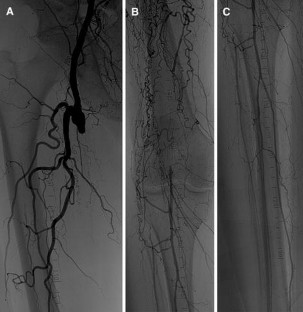

Percutaneous mechanical thrombectomy (PMT) is now established as an alternative treatment of acute arterial occlusions in addition to fibrinolysis and surgical thrombectomy. The objective of this retrospective study was the investigation of a rotational atherothrombectomy catheter in terms of safety and efficacy in the treatment of acute and subacute femoropopliteal bypass occlusions.

Forty-two patients (average age 65.8 ± 9.1 years) with acute (<14 days [n = 31]) and subacute (14–42 days [n = 11]) femoropopliteal bypass occlusions were treated consecutively with a rotational debulking and removal catheter (Straub Rotarex). The average occlusion length was 28.4 ± 2.9 (24–34) cm. Thirty-four (81 %) patients underwent venous bypass, and 8 (19 %) patients underwent polytetrafluoroethylene bypass.

The technical success rate was 97.6 % (41 of 42). In 1 patient, blood flow could not be restored despite the use of the atherothrombectomy system. The average catheter intervention time was 6.9 ± 2.1 (4–9) min. Ankle-brachial index increased from 0.39 ± 0.13 to 0.83 ± 0.11 at discharge and to 0.82 ± 0.17 after 1 month (p < 0.05). There were a total of 2 (4.8 %) peri-interventional complications: One patient developed a distal embolism, which was successfully treated with local lysis, and another patient had a small perforation at the distal anastomosis, which was successfully treated with a stent.

PMT with the Rotarex atherothrombectomy catheter represents a safe and effective option in the treatment of acute and subacute femoropopliteal bypass occlusions because it can quickly restore blood flow.